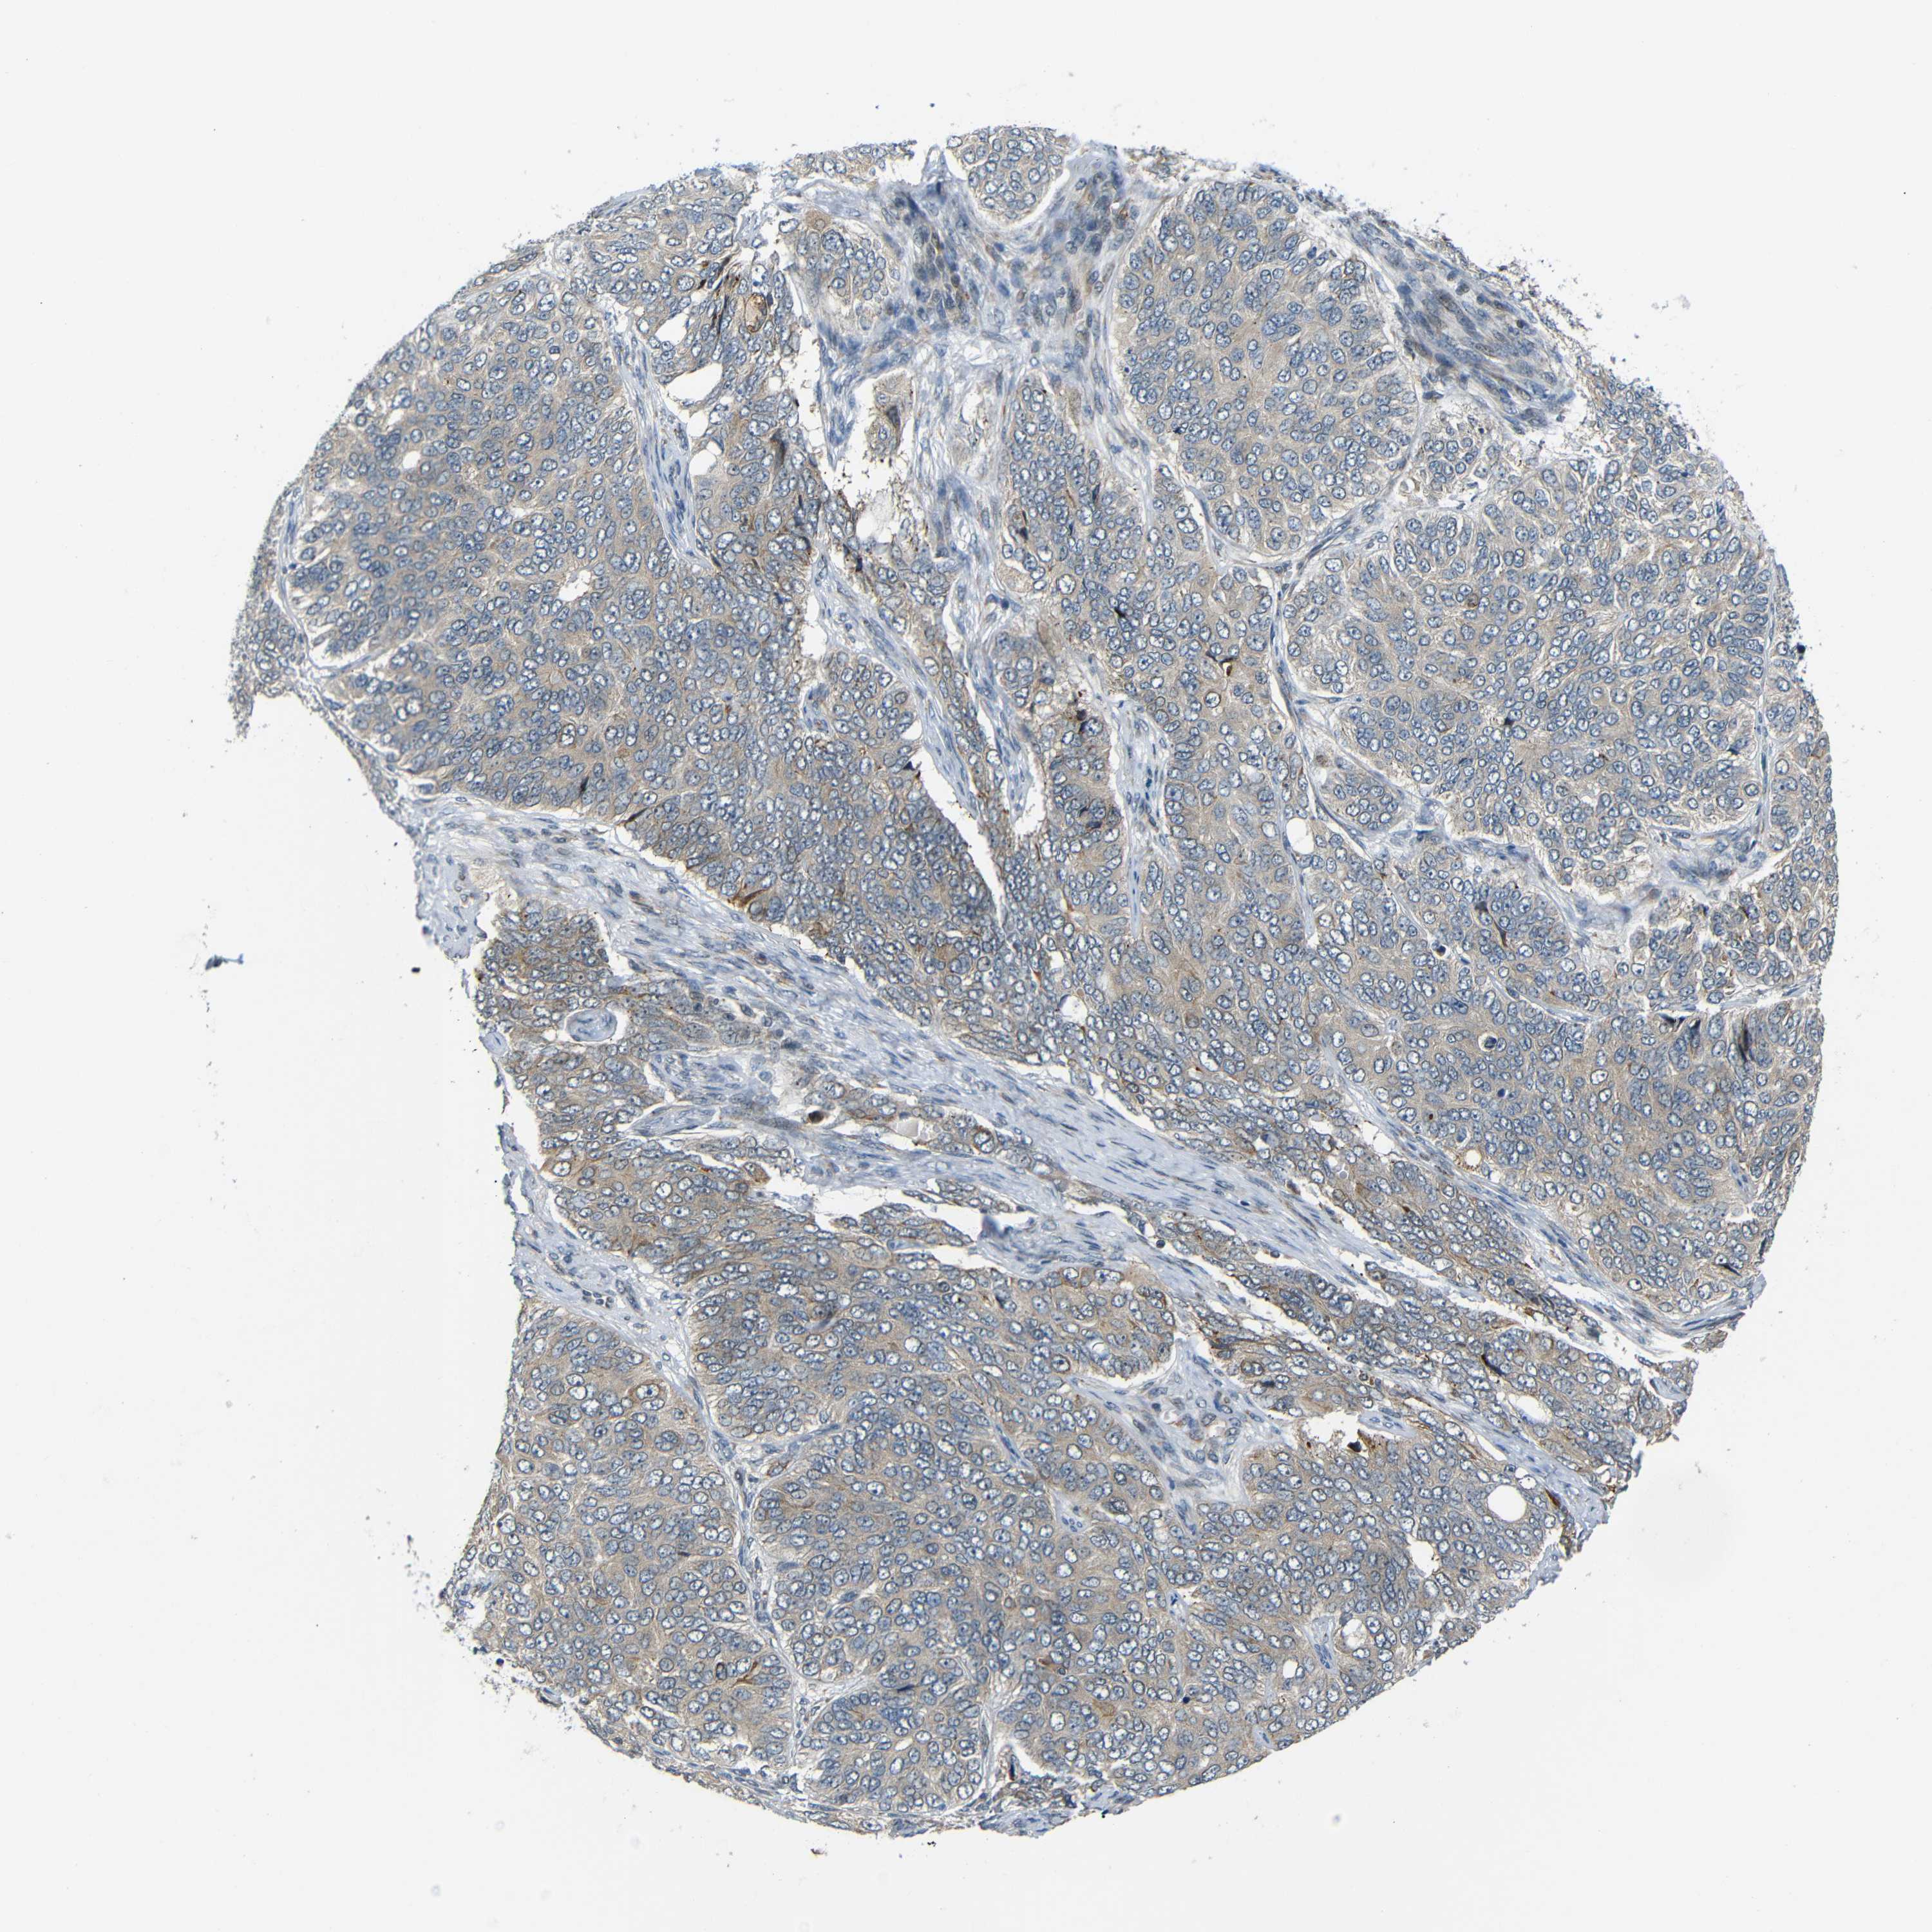

OVARIAN CANCER - Protein expressioni

A mouse-over function shows sample information and annotation data. Click on an image to view it in a full screen mode. Samples can be filtered based on level of antibody staining by selecting one or several of the following categories: high, medium, low and not detected. The assay and annotation is described here.

Note that samples used for immunohistochemistry by the Human Protein Atlas do not correspond to samples in the TCGA dataset.

Antibody stainingi

Antibody staining in the annotated cell types in the current human tissue is reported as not detected, low, medium, or high, based on conventional immunohistochemistry profiling in selected tissues. This score is based on the combination of the staining intensity and fraction of stained cells.

Each image is clickable and will lead to virtual microscopy that enables deeper exploration of all samples and also displays staining intensity scores, fraction scores and subcellular localization as well as patient and tissue information for each sample.

Antibody HPA013328

Staining

High

Medium

Low

Not detected

Intensity

Strong

Moderate

Weak

Negative

Quantity

>75%

75%-25%

<25%

None

Location

Nuclear

Cytoplasmic/membranous

Cytoplasmic/membranous,nuclear

Cystadenocarcinoma, serous, NOS

Carcinoma, endometroid

Cystadenocarcinoma, mucinous, NOS

Carcinoma, NOS